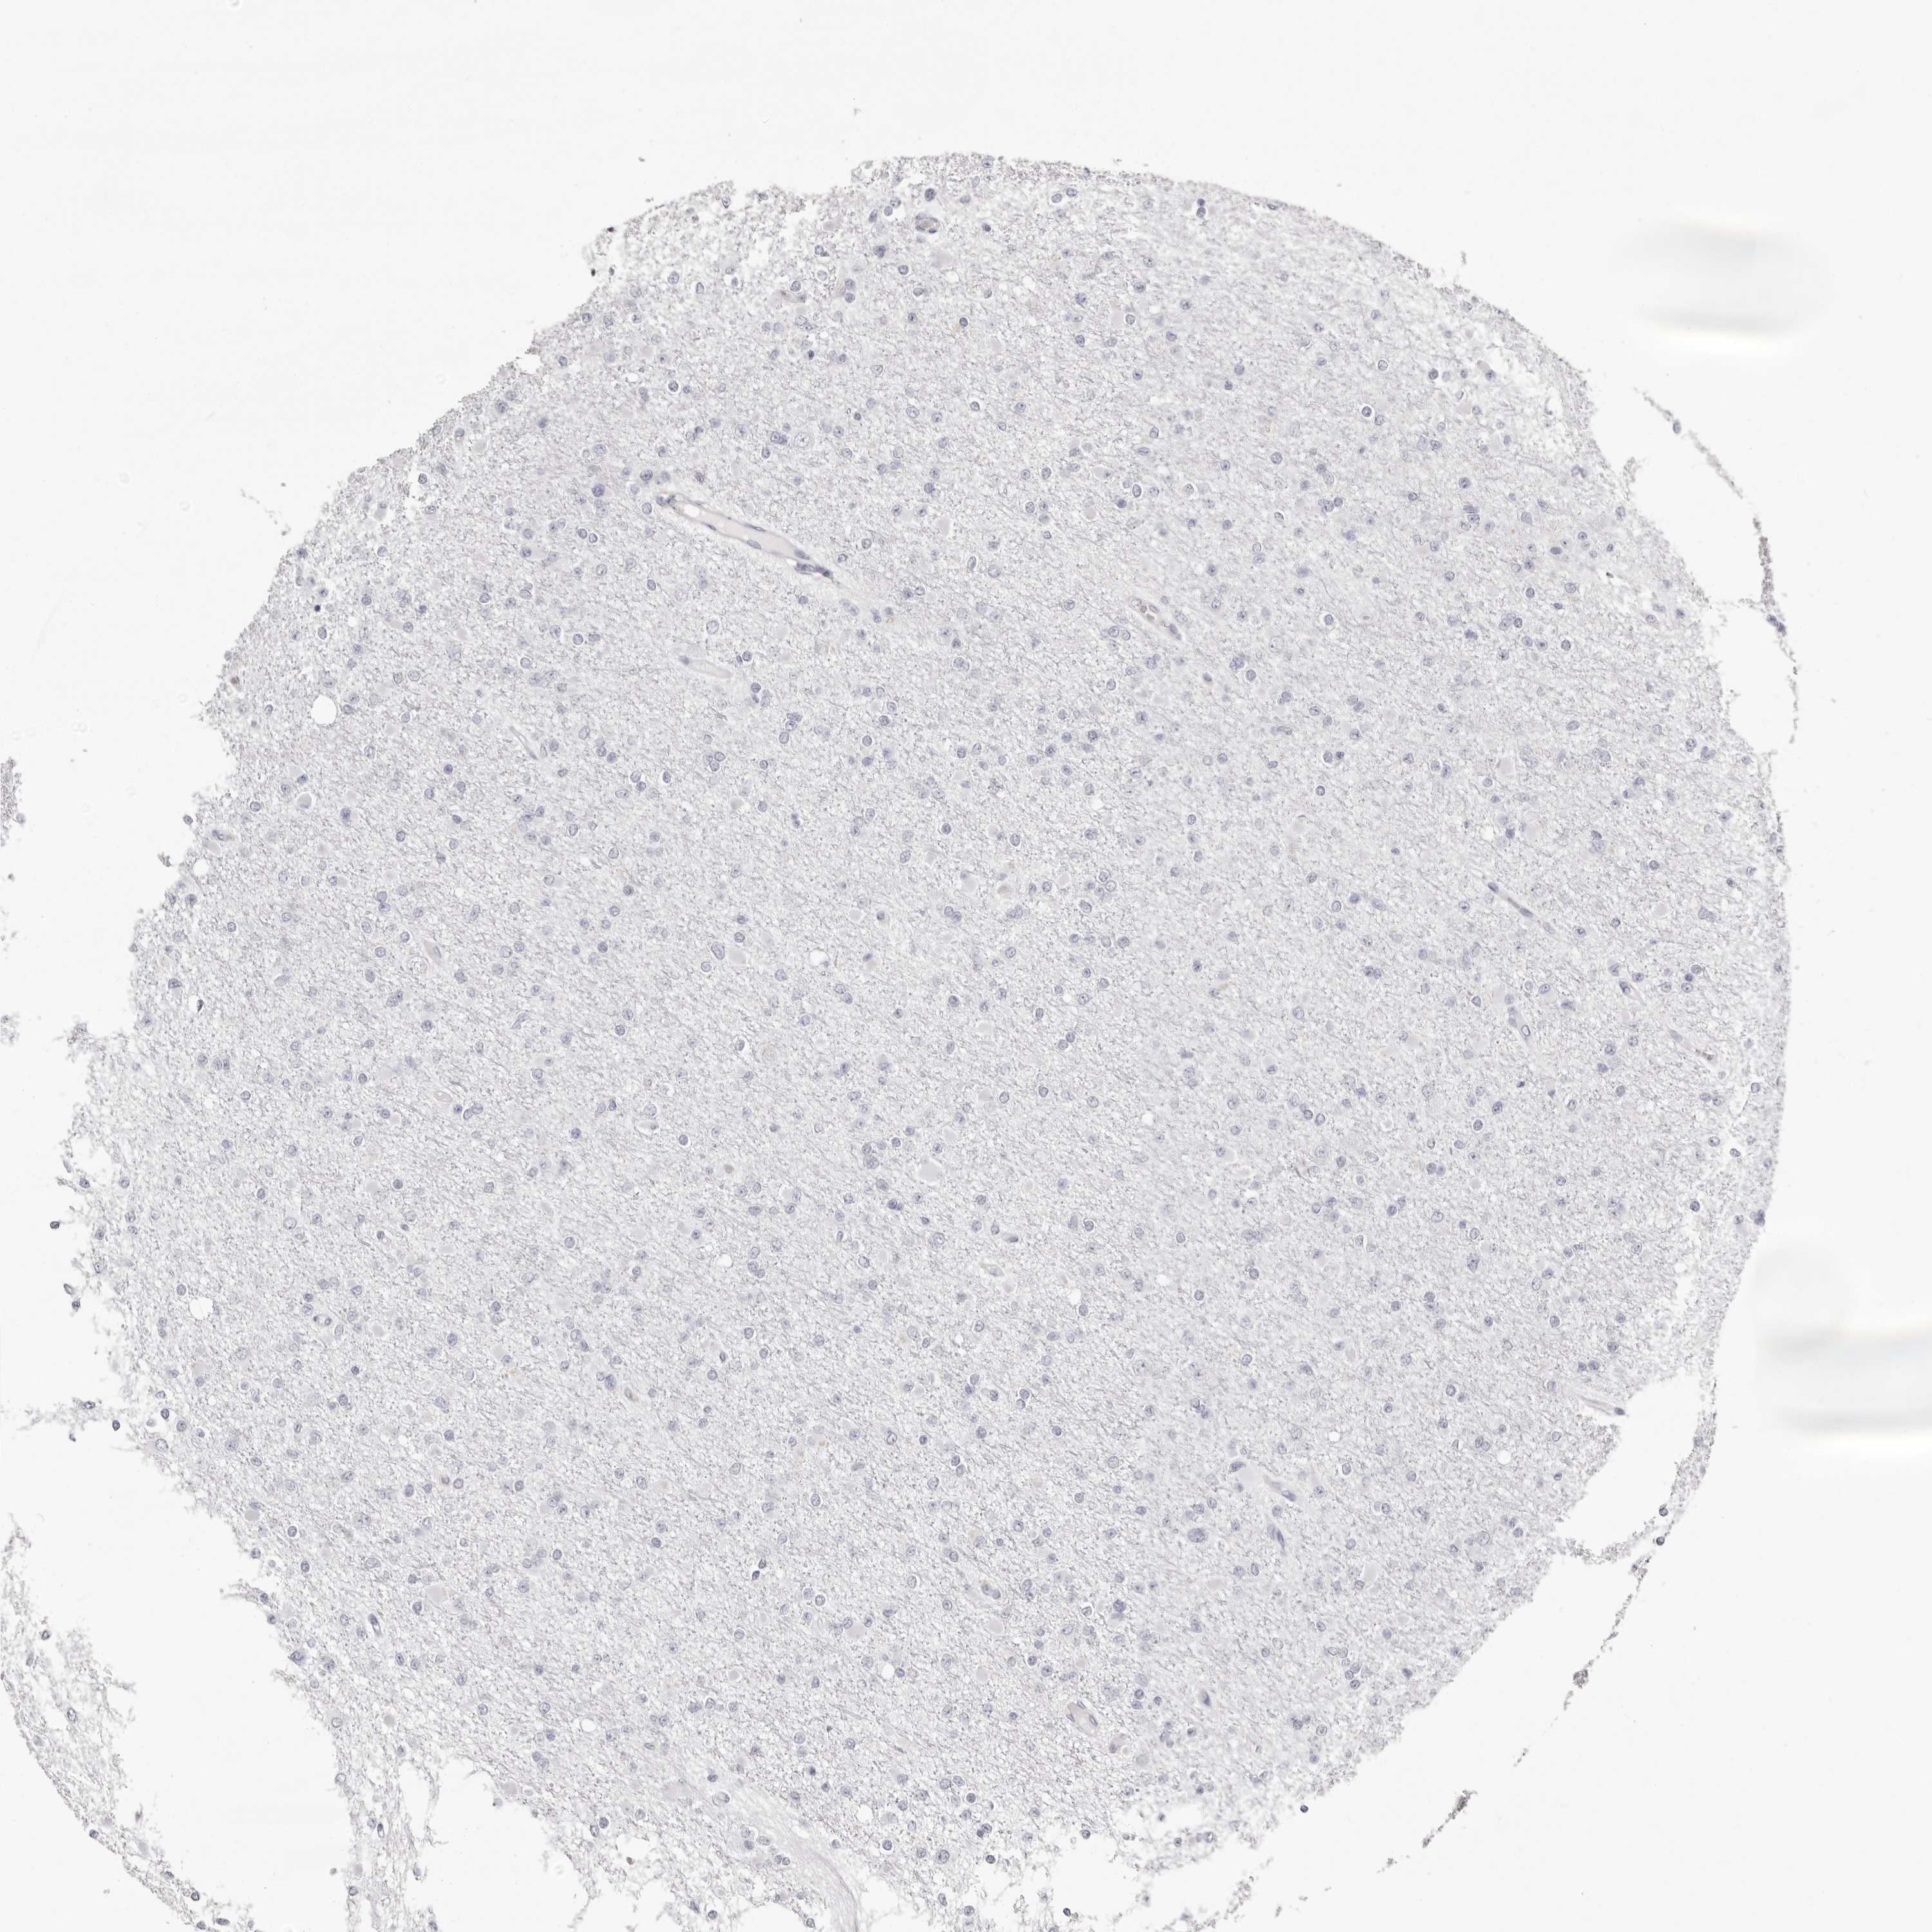

GLIOMA - Protein expressioni

A mouse-over function shows sample information and annotation data. Click on an image to view it in a full screen mode. Samples can be filtered based on level of antibody staining by selecting one or several of the following categories: high, medium, low and not detected. The assay and annotation is described here.

Note that samples used for immunohistochemistry by the Human Protein Atlas do not correspond to samples in the TCGA dataset.

Antibody stainingi

Antibody staining in the annotated cell types in the current human tissue is reported as not detected, low, medium, or high, based on conventional immunohistochemistry profiling in selected tissues. This score is based on the combination of the staining intensity and fraction of stained cells.

Each image is clickable and will lead to virtual microscopy that enables deeper exploration of all samples and also displays staining intensity scores, fraction scores and subcellular localization as well as patient and tissue information for each sample.

Antibody HPA028688

Staining

High

Medium

Low

Not detected

Intensity

Strong

Moderate

Weak

Negative

Quantity

>75%

75%-25%

<25%

None

Location

Nuclear

Cytoplasmic/membranous

Cytoplasmic/membranous,nuclear

Glioma, malignant, High grade

Glioma, malignant, Low grade

Glioblastoma, NOS